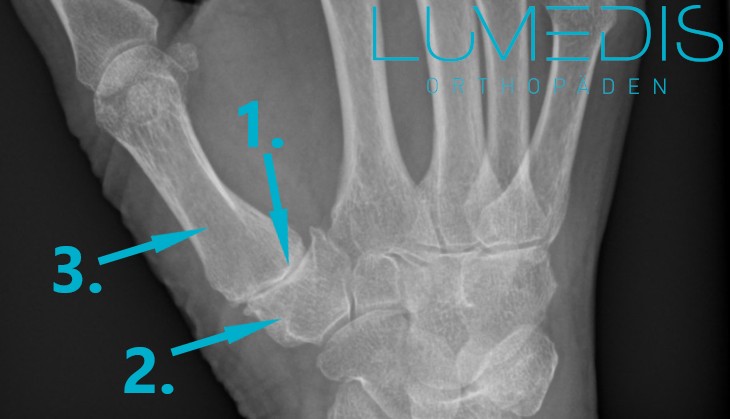

Grünholzfraktur am Handgelenk beim Kind

Abbildung eines Grünholzbruchs